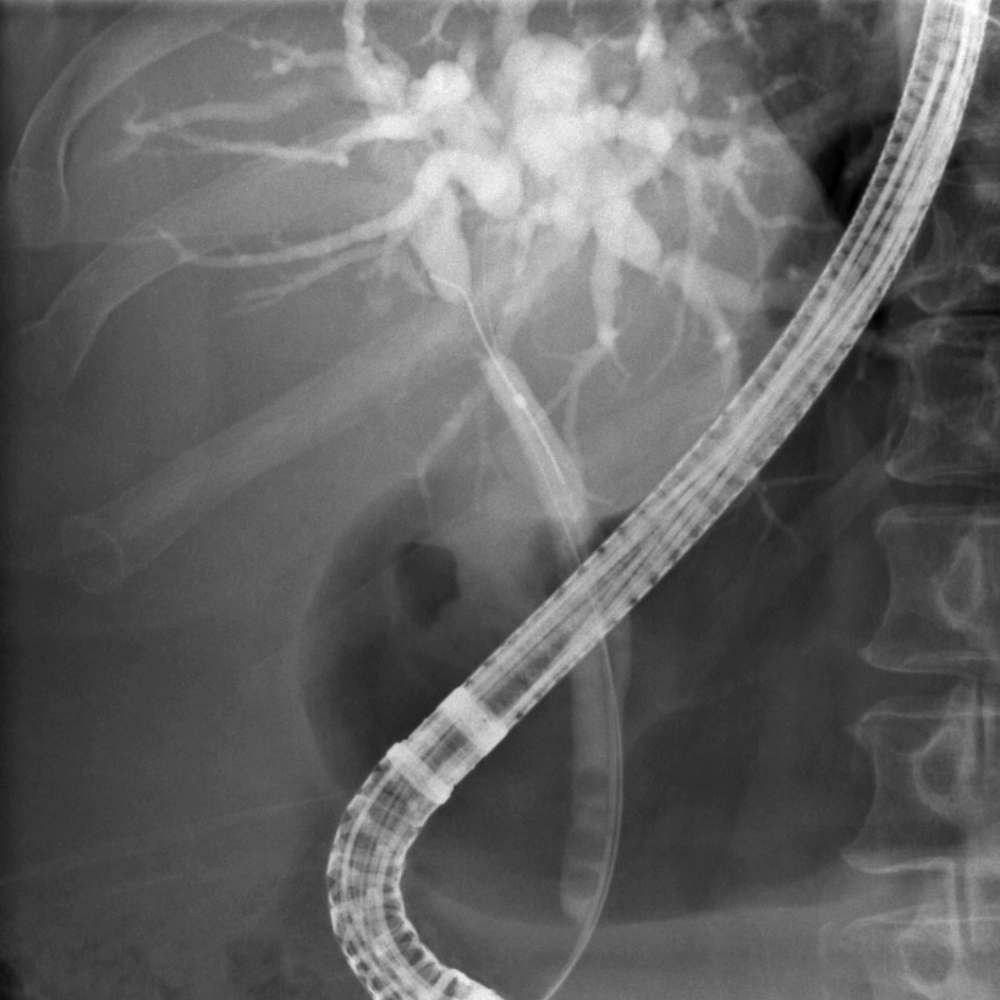

2. Targeted selective cannulation of both hepatic ducts in cases of Klatskin tumors.

Case 2